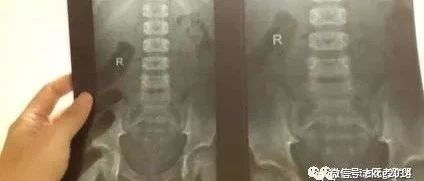

儿童隐性脊柱裂与遗尿症